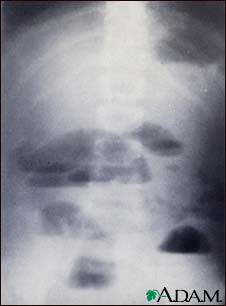

Small bowel obstruction - X-ray

X-rays of the abdomen are important in diagnosing the presence of small bowel obstruction. When obstruction occurs, both fluid and gas collect in the intestine. They produce a characteristic pattern called "air-fluid levels". The air rises above the fluid and there is a flat surface at the "air-fluid" interface.